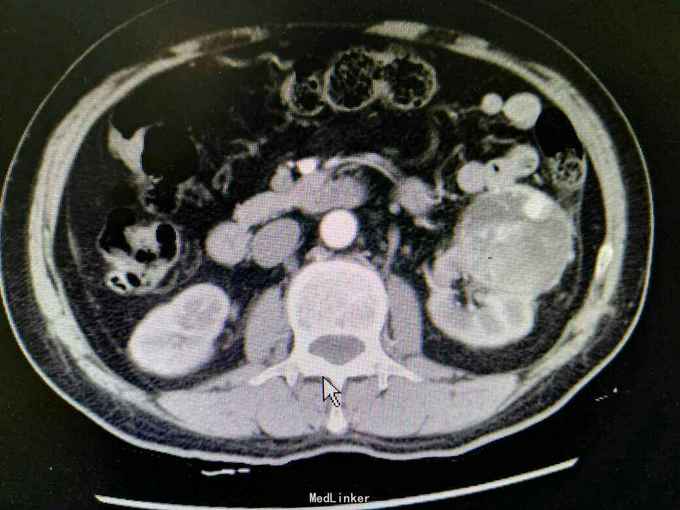

反复左腰酸痛不适5年,无血尿,无尿频尿急尿痛。外院B超:左肾囊肿。入院治疗。

体查未见明显异常。 CT:左肾外生性肿物,6.5x5.7cm,考虑肾癌 ECT:双肾功能良好。

诊断:左肾肿物 肾癌? 治疗:拟行腹腔镜左肾部分切除术。

讨论:肿瘤较大,适宜行部分切除还是根治性切除?